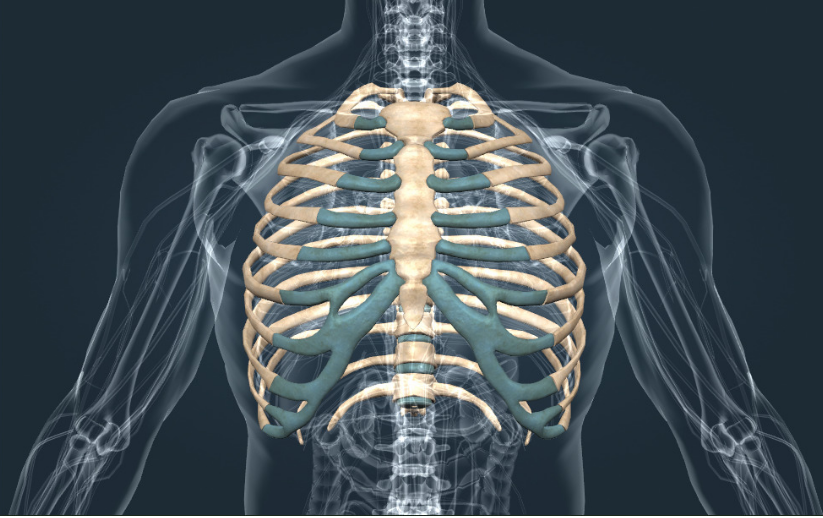

Якщо звернутися до базової анатомії, то стандартна кількість ребер у людини становить 24 — це 12 пар, розташованих по обидва боки грудної клітки. Вони формують кістковий захист для серця, легень і великих судин, створюючи стійкий і водночас рухомий каркас.

Кожна дугоподібна пластина складається з двох частин — кісткової та хрящової. Тверда основа забезпечує міцність, а гнучка частина — рухливість. Перші сім пар з’єднані з грудниною безпосередньо, інші — опосередковано або взагалі не мають з нею з’єднання.

1. Перші 7 пар — істинні. Міцно з’єднуються з грудниною індивідуальними хрящами, утворюючи жорсткий каркас.

2. Наступні 3 пари — несправжні. Приєднуються до груднини через спільну хрящову дугу, забезпечуючи рухливість середньої частини грудної клітки.

3. Останні 2 пари — вільні. Не з’єднуються з грудниною, закінчуються в м’яких тканинах, легко зміщуються при навантаженнях.